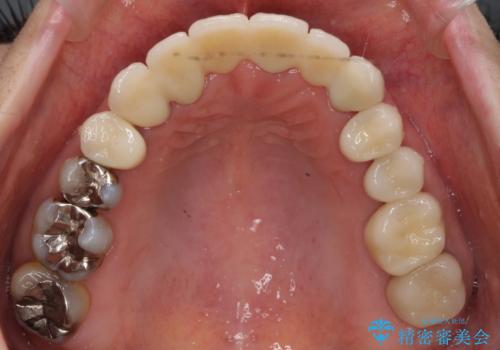

ブリッジの支台歯は、根の再治療を含めて行なっています。

下の歯は、患者様の希望によりホワイトニングを行なっています。

根の治療からやり直して新しいブリッジにしています。